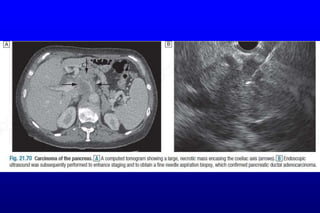

 The diagnosis is usually made by ultrasound and contrast-enhanced CT

 EUS or laparoscopy with laparoscopic ultrasound will define tumour size,

involvement of blood vessels& metastatic spread.

 In patients unsuitable for surgery because of advanced disease, frailty or

comorbidity, EUS- or CT-guided cytology or biopsy can be used to confirm

the diagnosis.

Pancreatic cancer: Investigations The diagnosis is usually made by ultrasound and contrast-enhanced CT  Diagnosis in non-jaundiced patients is often delayed because presenting symptoms are relatively non-specific.  Fit patients with small, localised tumours should undergo staging to define operability.  EUS or laparoscopy with laparoscopic ultrasound will define tumour size, involvement of blood vessels& metastatic spread.  In patients unsuitable for surgery because of advanced disease, frailty or comorbidity, EUS- or CT-guided cytology or biopsy can be used to confirm the diagnosis.  MRCP& ERCP are sensitive methods of diagnosing pancreatic cancer& valuable when the diagnosis is in doubt, although differentiation between cancer& localised chronic/AI pancreatitis can be difficult.  The main role of ERCP is to insert a stent into the common bile duct to relieve obstructive jaundice in inoperable patients.